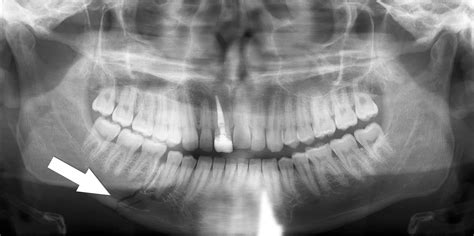

• X-Rays: X-rays are commonly used to visualize the bone and identify fractures.

• CT Scans: In more complex cases, a CT scan may be ordered to provide a detailed view of the jaw and surrounding structures.

• Physical Examination: The doctor will examine the jaw and face for signs of injury, such as swelling, bruising, and misalignment.